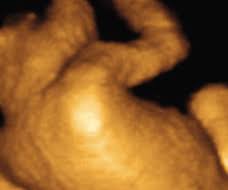

You may even feel her more as she gets stronger and more cramped in your uterus. Aug 26, 2019 · the baby does not need to move 10 times every two hours, but they should have a couple of active hours each day. 32 weeks to 35 weeks. Sep 02, 2010 · i am 27 weeks and hardly feel baby move, mabye once a day, 2 or 3 movemnets, i have tried everything! By 27 weeks pregnant, you can feel your baby move much more.

Many women find these movements comforting, and these often help strengthen the bonding process between mother and child. Is it normal for a baby to move every hour during pregnancy? Though your baby's movements may feel different, she shouldn't become less active. Sep 02, 2010 · i am 27 weeks and hardly feel baby move, mabye once a day, 2 or 3 movemnets, i have tried everything! With more brain tissue developing, your baby's brain is very active now. As your baby grows and has less room to move, you may notice that the type of movement you feel changes, perhaps becoming slower but lasting longer. 32 weeks to 35 weeks. By 27 weeks pregnant, you can feel your baby move much more. How often should your baby move at 28 weeks? Jul 13, 2009 · hey ladies i feel like at the moment i am just a constant worryer when it comes to my wee baby, i'm 27 weeks and wondering how often i should be feeling him kick, as it only seems to be a couple of times a day at the mo! My doctor says not to worry bu when should i. How does your baby move at 32 weeks? Also this may sound really strange but my bump seems to…

By 27 weeks pregnant, you can feel your baby move much more. My doctor says not to worry bu when should i. How does your baby move at 32 weeks? You may even feel her more as she gets stronger and more cramped in your uterus. Many women find these movements comforting, and these often help strengthen the bonding process between mother and child. Jul 13, 2009 · hey ladies i feel like at the moment i am just a constant worryer when it comes to my wee baby, i'm 27 weeks and wondering how often i should be feeling him kick, as it only seems to be a couple of times a day at the mo! Sep 02, 2010 · i am 27 weeks and hardly feel baby move, mabye once a day, 2 or 3 movemnets, i have tried everything! Also this may sound really strange but my bump seems to…